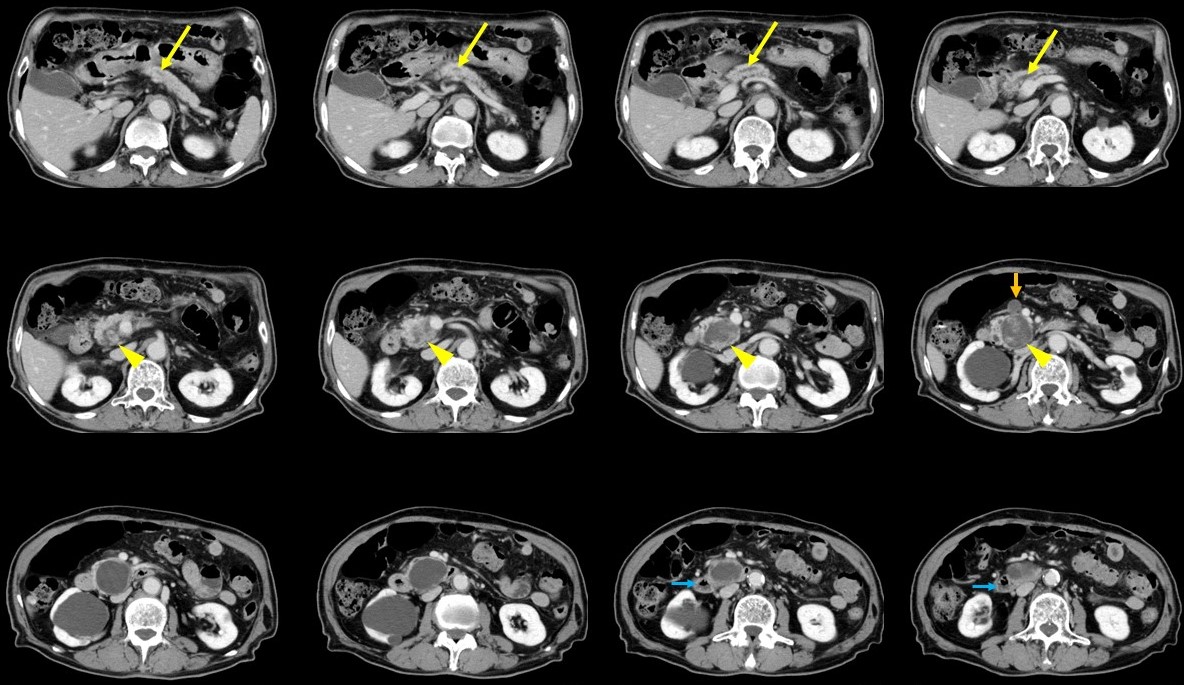

101A30 膵嚢胞性腫瘍 国試 M3E Medical

膵臓の嚢胞性病変 Dr. Tomの徒然日記

膵のう胞・IPMNがありますと医師に言われたら【患者さん向けの解説】 EUS channel

膵嚢胞性腫瘍(IPMN, MCN, SPN, SCNなど)の外科治療 国立がん研究センター 中央病院

膵臓の嚢胞性病変 Dr. Tomの徒然日記

嚢胞ってどんなもの?. 嚢胞とは体内にできる袋状の病変(病気によって起こる体の変化)で、その中には液状の内容物が入っています 。. ほとんどの嚢胞はその内側が上皮によって覆われています。. ちなみに、 内容物が固体の場合は嚢腫(のうしゅ) と.. 膵のう胞【すいのうほう】とは、膵臓の中や周りに いろんな大きさの「袋」 ができる病気です。 ほとんど 症状がなく 、嚢胞の 種類によって治療が異なる ので、詳しく調べる必要があります。 膵のう胞は、どんな病気? 膵のう胞【すいのうほう】とは、 膵臓の中や周り に いろんな大きさの「袋」 ができる病気です。 袋の中には、液体やねばねばとした液などが溜まっています。 CTやお腹のエコー検査などをして、 偶然発見 されることの多い病気です。 膵のう胞は、すぐに手術が必要なものから定期的に診察が必要なものまで様々で、種類が何であるかを詳しく調べる必要があります。 全人口の約2~3%の人が、膵のう胞を合併しているという報告もあり、決してまれな病気ではありません。